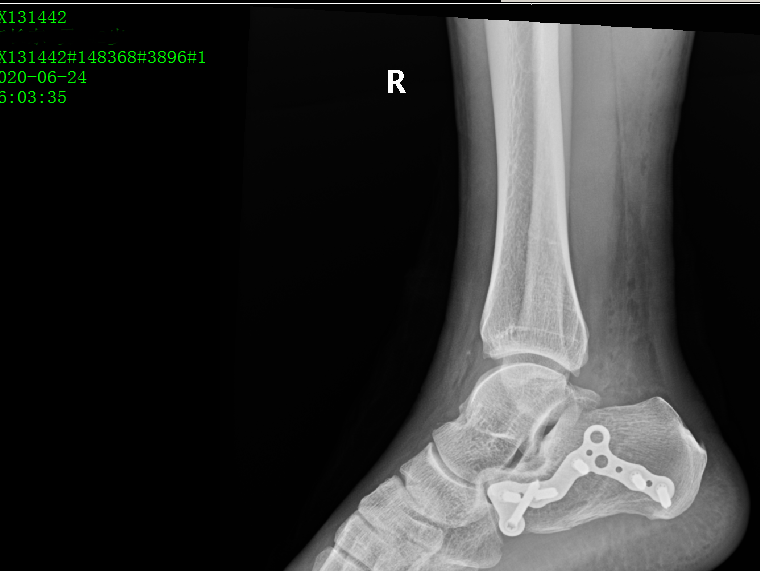

术后影像: